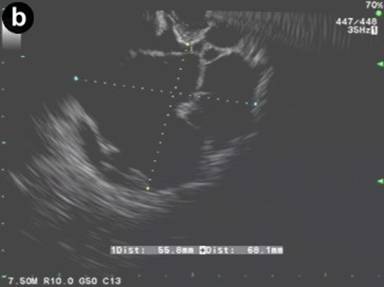

The patient was referred to our institution after a CT scan four months later showed the peripancreatic cyst stable in size measuring 9.0x4.5 cm (Figure 2a). Curved linear-array EUS showed a multiseptated cystic process near the head of the pancreas. The pancreas demonstrated some lobularity but did not meet EUS criteria for chronic pancreatitis (Figure 2b). The lesion was aspirated using the 19 gauge EUS-FNA needle and 5 mL of milky-white fluid was obtained. Laboratory analysis of the cystic fluid revealed a CEA of 2.0 ng/mL and an amylase of 276 U/L. Cytology was negative for malignancy, showed only benign appearing lymphocytes on the smear, and felt to be consistent with diagnosis of pancreatic cystic lymphangioma. Given the small amount of fluid aspirated, a triglyceride level was unable to be obtained due to partial solidification of material prior to analysis. No further diagnostic testing such as immunostaining was performed and patient was referred for surgical evaluation. Unfortunately, the patient failed to make this appointment and was lost to follow-up.

Figure 2. a. Contrast enhanced abdominal CT scan showing a cystic lesion adjacent to the body of the pancreas and extending into the porta hepatis from Case #2. b. Linear EUS image showing the anechoic cyst with several thin septae from the same patient. |